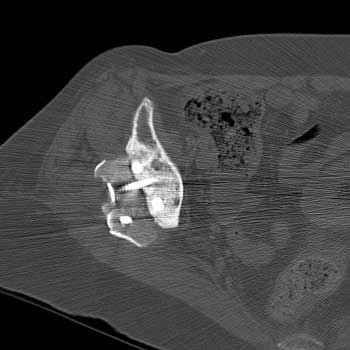

Mass in patient with modular endoprosthesis placed after resection of femur for osteosarcoma. Axial (fig A) and coronal reformatted images (fig B) clearly demonstrate mass adjacent to modular endoprosthesis. 14 gauge core needle biopsy performed under CT guidance (fig C) demonstrated recurrent osteosarcoma